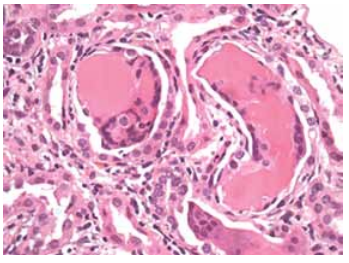

Mulher de 65 anos, hipertensa, foi avaliada para dorsalgia torácica, injúria renal aguda, anemia e hipercalcemia. A paciente usava ibuprofeno 3-4 vezes/dia, losartana e clortalidona. O exame de urina mostrou traços de proteína, e a relação proteína-creatinina na urina foi de 4,8 mg/mg. As cadeias leves λ livres de soro foram de 726 mg/dL, e a relação κ/λ foi de 0,3. Apesar da hidratação intravenosa e da correção da hipercalcemia, sua função renal piorou, e foi iniciada hemodiálise e realizada uma biópsia renal.

(Hematoxilina e eosina; aumento original, ×400.Disponível em: https://www.ajkd.org)

Qual achado de biópsia renal provavelmente será observado nesta paciente?